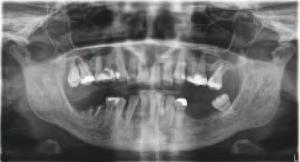

O pac entă de 61 an s-a prezentat la Per odont cs/Per odontal Prosthes s Cl n c d n cadrul Un vers ty of Pennsylvan a School of Dental Med cne dor nd în pr nc pal să a bă „d nț f xaț ” în locul protezelor mob le ex stente (f g. 1). După f nal zarea unu examen stomatolog c cupr nzător, nclus v exam narea extra- ș ntraorală, evaluarea pr n tomograf e computer zată cu fasc cul con c (CBCT), fotograf erea dentară ș întocm rea f șelor dentare, s-a creat un plan pentru real zarea une reab l tăr full-mouth folos nd mplantur ș proteze dentare f xe. Pac enta purta proteze totale moble retenț onate pe m n - mplantur atât la mand bulă, cât ș la max lar. În t mpul evaluăr n ț ale, ea ș -a expr mat preocupăr le legate de estet ca restaurăr lor ex stente în ceea ce pr vește expunerea g ng vală ș

1. Imaginea intraorală a protezelor existente retenționate de miniimplanturi la prezentarea inițială.

2. Pacienta prezenta expunerea excesivă a componentei gingivale din protezele existente.

3. Situația pretratament mandibulară edentată cu cele patru mini-implanturi existente.